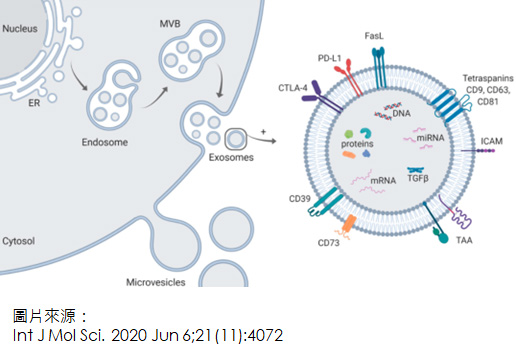

外泌體開發

Exosome development